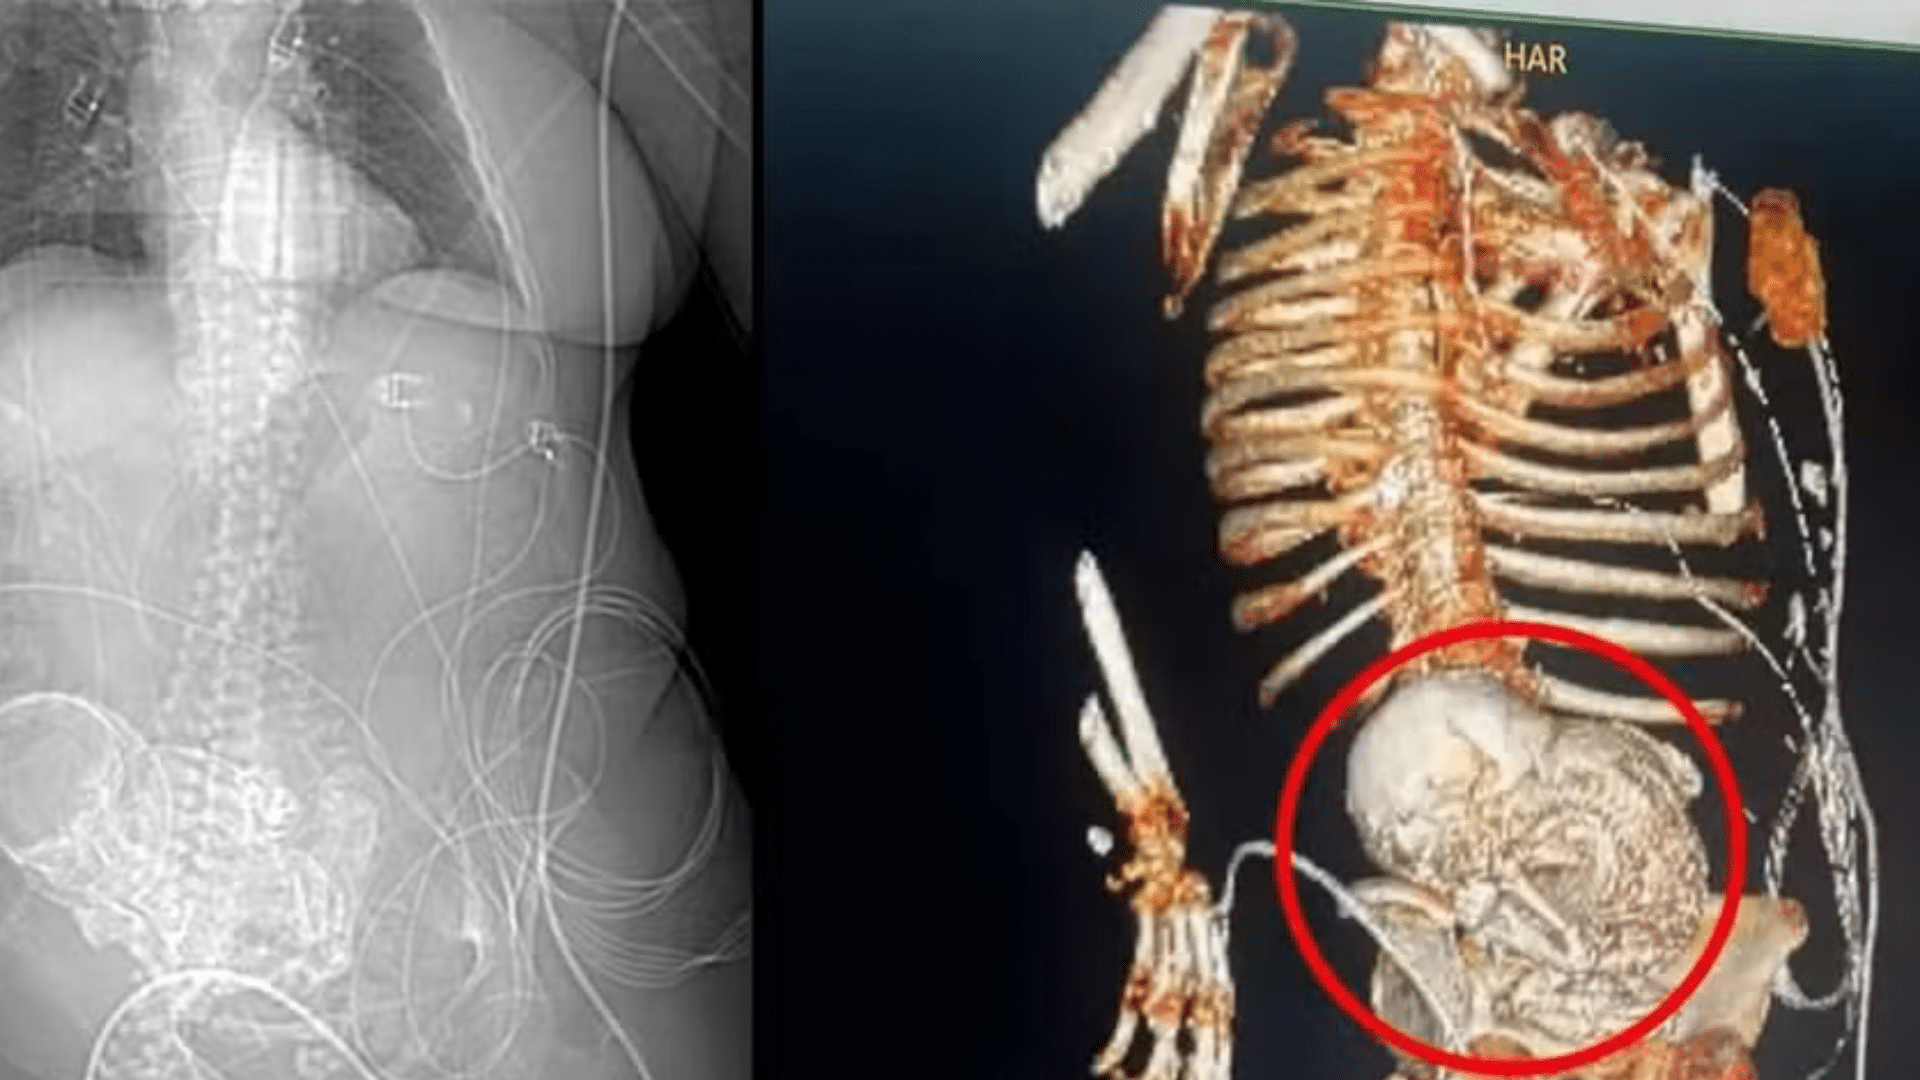

Uma idosa de 86 anos, residente na região sul de Mato Grosso do Sul, foi diagnosticada com uma condição extremamente rara após ser internada no Hospital Regional de Ponta Porã. A equipe médica constatou que a idosa carregava um “bebê de pedra” em seu abdômen, um feto calcificado que permaneceu lá por mais de 56 anos, desde sua última gestação.

A descoberta aconteceu quando a idosa deu entrada no hospital com dores abdominais e um quadro de infecção grave em 14 de março deste ano. Após uma tomografia, os médicos identificaram o feto calcificado na região abdominal da paciente.

A equipe de obstetrícia do hospital realizou uma cirurgia para a remoção do feto calcificado, mas infelizmente, após o procedimento, a idosa foi encaminhada para a Unidade de Tratamento Intensivo (UTI) devido a complicações decorrentes da infecção grave e acabou falecendo no dia seguinte, em 15 de março.

O caso foi considerado extremamente raro pelos especialistas, que apontaram a condição como litopedia, uma forma rara de gravidez ectópica. O feto de uma gravidez abdominal não reconhecida morre e se calcifica dentro do corpo da mãe, podendo permanecer não detectado por décadas e causar complicações futuras.